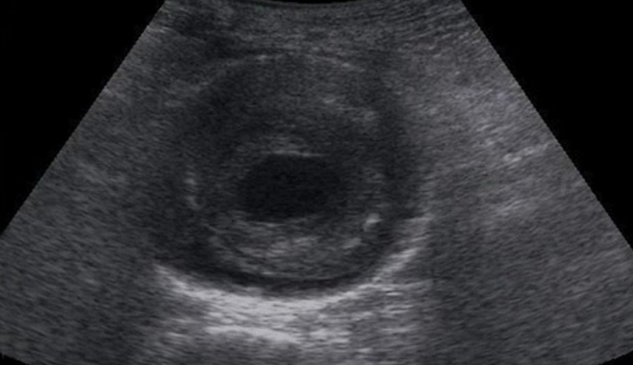

Incidentaloma: Gallbladder Polyps

What is your differential for a gallbladder polyp?

What do we do with this common incidental finding?

Read time: 4-5 minutes.